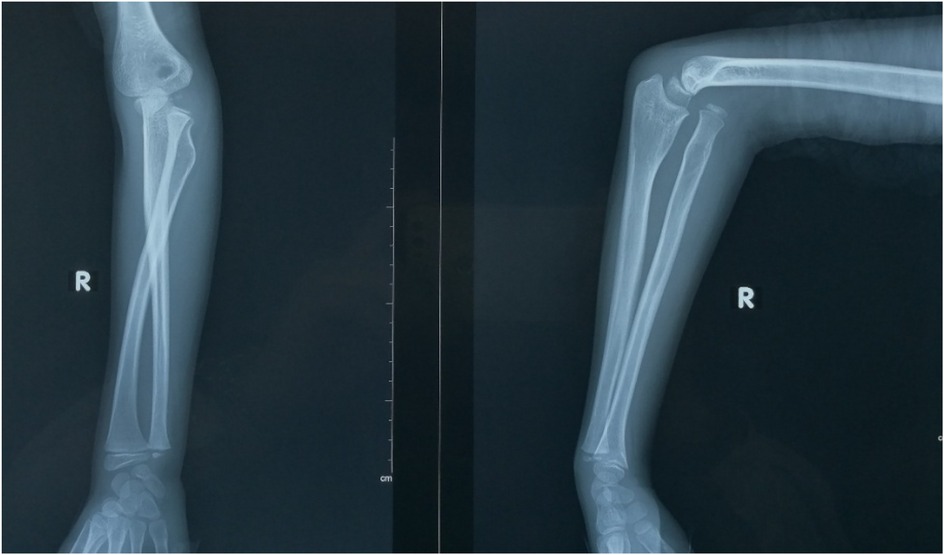

Objective: To investigate and analyze the application value of elbow arthrography in the treatment of chronic radial head dislocation in children. Methods: From January 2014 to January 2017, 15 children with chronic anterior radial head dislocation were treated (11 boys, 4 girls; average age 9 years, range 3-11 years). Intraoperative elbow arthrography was performed to assess the position of the radial head relative to the joint capsule. The nature of the dislocation was confirmed by opening the joint capsule to directly observe the relationship between the radial head and capitellum, as well as the morphology of the radial head. Reduction of the radial head was achieved via proximal ulnar osteotomy, and fixation was performed using a plate and screws with or without Kirschner wires (K-wires). Results: Elbow arthrography showed the radial head was located within the joint capsule in 12 cases and outside the capsule in 3 cases. Among the cases: All 8 congenital dislocations had the radial head within the joint capsule. Of the 7 traumatic dislocations, 4 had the radial head within the capsule and 3 outside. Direct inspection after capsulotomy confirmed the arthrography findings and revealed characteristic morphological differences. In congenital dislocations, there was no scar tissue between the radial head and capitellum, and the radial head fovea was shallow and flat. In traumatic dislocations, obvious scar tissue was present between the radial head and capitellum, and the radial head fovea was distinct. Follow-up ranged from 9 months to 4 years (average 2 years 5 months). Postoperative radiographs showed no cases of radial head re-dislocation or subluxation. Postoperative elbow range of motion improved in all patients, with no reports of pain or functional instability. Conclusion: Elbow arthrography serves as a valuable adjunct for differentiating between congenital and traumatic radial head dislocations, thereby informing both surgical strategy and the decision for supplemental fixation. When stable bony alignment is achieved, proximal ulnar osteotomy without annular ligament reconstruction represents an effective management strategy for chronic radial head dislocation in children.